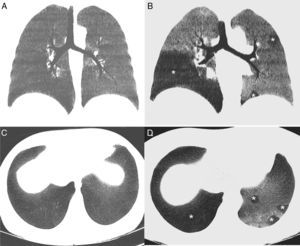

A) Reconstrucción coronal minIP de la TC de tórax en inspiración, en la que se observa un parénquima pulmonar homogéneo con una atenuación uniforme. B) Reconstrucción coronal minIP de la TC de tórax en espiración, en la que se identifica un patrón en mosaico del parénquima pulmonar, apreciándose áreas geográficas de baja densidad (asterisco), que se alternan con otras zonas de mayor atenuación. Las áreas de baja densidad (que afectan especialmente al lóbulo inferior derecho y de forma parcheada al pulmón izquierdo) corresponden a zonas de atrapamiento aéreo, mientras que las áreas de mayor densidad corresponden a parénquima pulmonar normal. C) Reconstrucción axial minIP de TC de tórax en inspiración, en la que se observa un parénquima pulmonar homogéneo. D) Reconstrucción axial minIP de la TC de tórax en espiración, en la que se visualizan áreas geográficas de baja densidad (asteriscos) en relación con áreas de atrapamiento aéreo.

Presentamos el caso de una mujer de 44 años con antecedentes de una leucemia mieloide aguda, tratada con TPH de donante no emparentado 6 meses antes, que consultó por disnea y tos seca. Como complicación del TPH, la paciente presentó una viremia transitoria por citomegalovirus y una EICH cutánea grado III, que respondió favorablemente al tratamiento con corticoides. Una radiografía de tórax no detectó opacidades parenquimatosas, pero una TCi y TCe de tórax demostró la presencia en la fase espiratoria de un llamativo patrón en mosaico del parénquima pulmonar identificándose múltiples áreas de atrapamiento aéreo en ambos pulmones (fig. 1), al tiempo que descartó complicaciones infecciosas. Las zonas de atrapamiento aéreo en la TC se ponen mejor de manifiesto utilizando la proyección de mínima intensidad (minIP), un algoritmo de visualización de imágenes que realza las áreas de menor atenuación. Las pruebas de función pulmonar (PFP) arrojaron una leve disminución (<20%) del volumen espiratorio forzado en el primer segundo (FEV1) y un aumento del volumen residual (VR) (138%) con respecto a los valores pre-TPH. Una fibrobroncoscopia no mostró alteraciones y el lavado broncoalveolar descartó infecciones oportunistas. Ante estos hallazgos se emitió el diagnóstico de BC, respondiendo favorablemente (estabilización de las pruebas funcionales) al tratamiento con corticoides sistémicos a dosis altas.